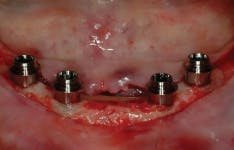

All-on-4 advocates claim that this type of treatment plan reduces cost and saves treatment time, but with the introduction of the ScrewIndirect one-piece implant that provides the implant, abutment, comfort cap, and transfer at a fraction of the cost of the implant alone from all the major implant companies, the economics argument for using the minimum number of implants is no longer valid. The ScrewIndirect screw-receiving platform allows splinting of implants that have up to 40 degree divergence, allowing distal angulations of up to 20 degrees if desired. Placement of five implants in the lower symphysis and six anterior to the maxillary sinuses can be relatively straight and still support adequate length of distal cantilevers. Four ScrewIndirect implants can also be placed, as shown below, splinted with a distal attachment for retention of an overdenture, but providing the patient with a fixed-detachable prosthesis that eliminates the need for a removable prosthesis is a more natural solution to restoring an edentulous jaw.

The ScrewIndirect one-piece implant offers a 3.0 mm D implant with adequate strength. All four diameter options (3.0 mm, 3.7 mm, 4.7 mm and 5.7 mm) have the same 5 mm D multi-unit platform. The 3.0 mm D implant allows treatment of narrow ridges and simplifies accurate placement during flapless surgery. Providing teeth in one day to edentulous patients and immediate implant placement following extractions is becoming the treatment of choice. The patient's existing denture is converted to a fixed-detachable prosthesis immediately following implant placement. This is accomplished by attaching titanium sleeves to the implants that project through holes cut in the denture and attached them to the denture with cold-cure acrylic followed by shortening the denture flanges.